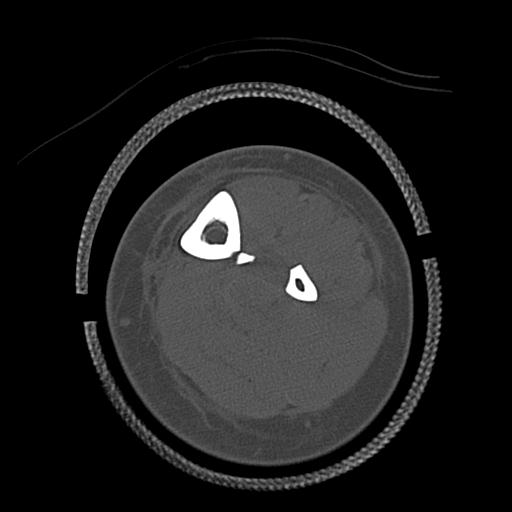

91983 11/16 左膝 2R 11/18 2R 55歳男性 脛骨骨切り術